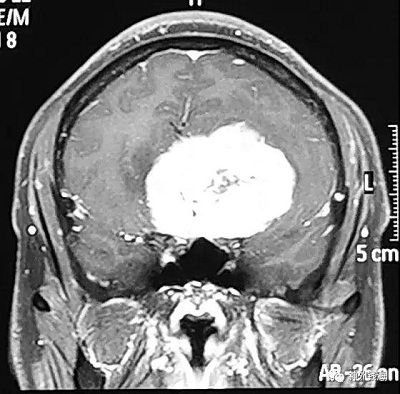

在临床工作中,我经常遇见这样的情况:患者视力一直不好,在眼科检查治疗了很长时间也不见效,眼科也的确没有发现异常情况。还有的患者月经紊乱,或者不孕不育,在妇产科及内分泌科治疗了一段时间,也是没有效果。后查了头部的核磁共振,才发现原来病因在颅内,鞍区已经有了一个很大的肿瘤。手术切除肿瘤以后,原来的眼睛或内分泌问题也逐步恢复了。这就是特别需要引起重视的,即颅内肿瘤可能表现为眼科或妇产科、内分泌科的疾病,如果忽略了头部检查,则可能遗漏了根本的病因,因而疗效只会是暂时的,或者是“久治不愈”。

尽管颅内肿瘤相对于眼科疾病、妇产科疾病及内分泌科疾病的发病率低,相对少见,但是在神经外科住院患者中,很大一部分患者以此为主要症状或首发症状。磁共振检查对人基本无损伤,无放射性,可以有效检查出上述颅内疾病。

首都医科大学三博脑科医院神经外科钱海特别提示眼科、妇产科及内分泌科的患者,如果遇到上面所说的情况,特别是伴有头痛的患者,请在医生指导下进行头部磁共振检查,可能会找到疾病的源头,从而达到满意的疗效。